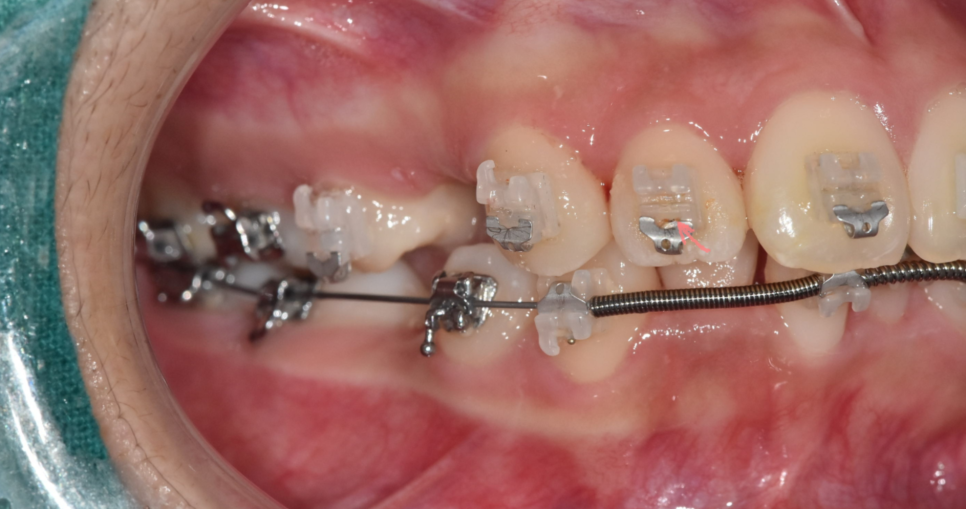

브라켓 사이사이를 꼼꼼하게 닦을 수 있는

치간 칫솔 사용

250509 양치가 잘 안되어 장치 내부에 음식물이 껴 있어요.

교정 중에도 약속 날짜에 맞춰 병원에 방문해주셔야합니다.

일반적으로는 교정 중에 치아 상태를 꾸준히 모니터링 하기 때문에

조기에 충치를 발견할 수 있지만

내원을 한동안 중단하게 되면

크기가 커져서 방문하는 경우가 많기 때문이죠.